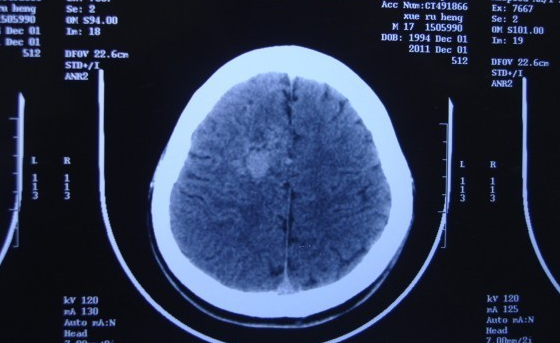

继发性癫痫的形成是由原来正常的大脑神经细胞及其网络,因与原发性致痫灶受损的细胞突触联系而被不断影响,最终获得了细胞癫痫样放电的异常过程。

一般认为癫痫发病的原因有脑外伤、肿瘤、血管畸形、血管阻塞、感染、中毒和缺氧等。但并非以上疾患都会出现癫痫,故应注意探索上述疾患病区是如何引起远隔病变区的神经元产生与原发灶相似的致痫性损害,出现相似的异常放电和癫痫临床表现。而这些继发灶代表了未受上述原发病灶直接影响,却产生了似癫痫细胞群。由此形成的继发性癫痫,是在经过治疗原发病灶已被消除后,而仍继续有癫痫发作或继续恶化的癫痫存在的原因。